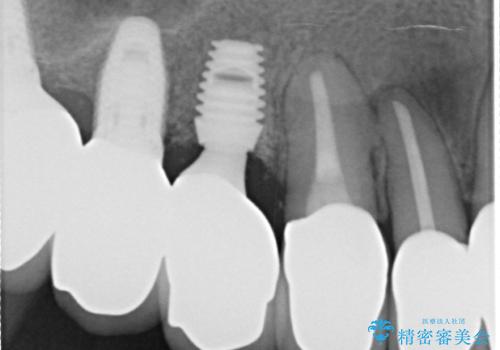

- 歯周外科・再根管治療後、クラウンを製作する。

・虫歯がとりきれていない

・接触部分がガタガタで適合の悪い金属

・全く無菌の努力がされていない根管治療

など、いい加減な治療は「治療」ではなく、むしろ医原性に歯の寿命を短くします。

かぶせ物の種類:PFZ standard